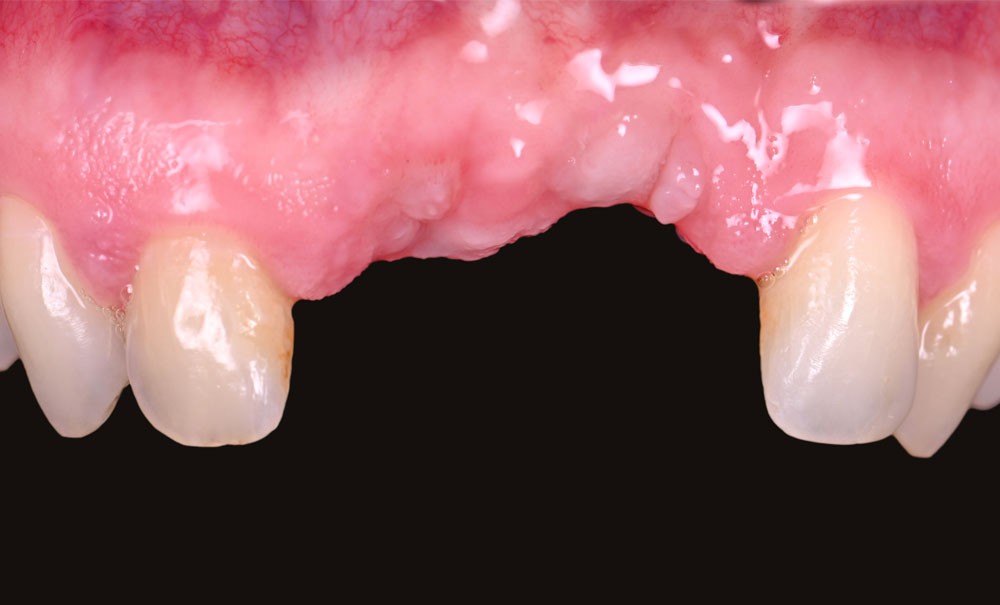

La chirurgie implantaire nécessite fréquemment des procédures de greffe osseuse pour pallier les déficits volumétriques et permettre un positionnement idéal des implants. Le défaut osseux peut être lié à de nombreux facteurs : extraction ancienne, prothèse amovible, séquelles iatrogènes. La technique de Split Bone Bloc (ou technique Shell), développée par F. Khoury, est une méthode efficace mais réservée à des praticiens expérimentés, en raison de sa technicité et de la morbidité associée à un prélèvement rétromolaire mandibulaire.

La chirurgie guidée dynamique permet, quant à elle, de prélever par piezochirurgie (Piezotouch, Mectron) de façon naviguée (fig. 3). Ainsi, le bloc peut être designé en amont sur le logiciel de planification implantaire pour correspondre parfaitement au défaut osseux en présence, et prélevé à l’identique sur la ligne oblique externe (fig. 4 à 8).